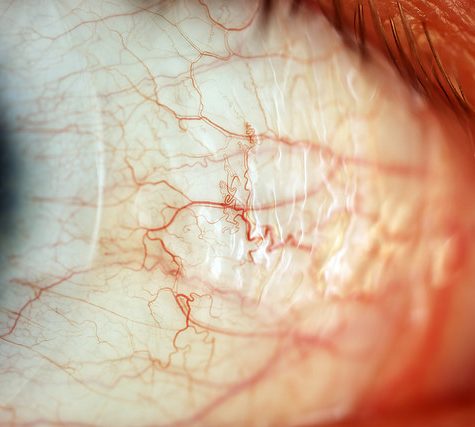

The sclera, also known as the white of the eye, is the opaque, fibrous, protective, outer layer of the eye containing mainly collagen and some elastic fiber.[2] In humans, the whole sclera is white, contrasting with the coloured iris, but in other mammals the visible part of the sclera matches the colour of the iris, so the white part does not normally show. In the development of the embryo, the sclera is derived from the neural crest.[3] In children, it is thinner and shows some of the underlying pigment, appearing slightly blue. In the elderly, fatty deposits on the sclera can make it appear slightly yellow.

The human eye is relatively rare for having an iris that is small enough for its position to be plainly visible against the sclera. This makes it easier for one individual to infer where another individual is looking, and the cooperative eye hypothesis suggests this has evolved as a method of nonverbal communication.

The sclera, also known as the white of the eye, is the opaque, fibrous, protective, outer layer of the eye containing mainly collagen and some elastic fiber.[2] In humans, the whole sclera is white, contrasting with the coloured iris, but in other mammals the visible part of the sclera matches the colour of the iris, so the white part does not normally show. In the development of the embryo, the sclera is derived from the neural crest.[3] In children, it is thinner and shows some of the underlying pigment, appearing slightly blue. In the elderly, fatty deposits on the sclera can make it appear slightly yellow.

The human eye is relatively rare for having an iris that is small enough for its position to be plainly visible against the sclera. This makes it easier for one individual to infer where another individual is looking, and the cooperative eye hypothesis suggests this has evolved as a method of nonverbal communication.